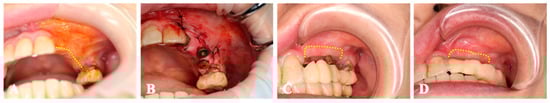

2.3. Surgical Procedure